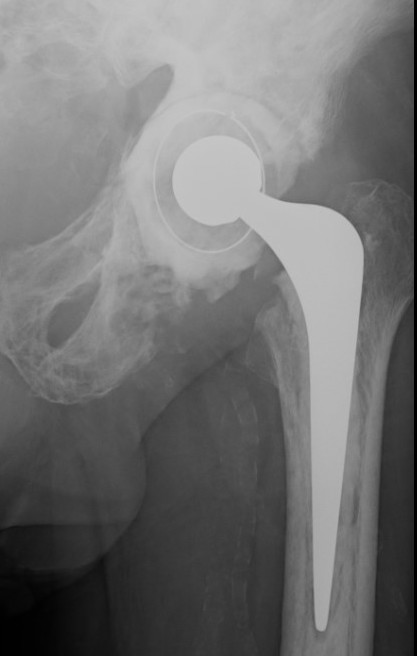

THA

Technical issues

Bleeding

- preoperative calcitonin / bisphosphonates / EPO / Iron

- intra-operative blood salvage system

Acetabulum

- difficult reaming due to hard bone

- protrusio - consider medial bone graft / cages / lateral offset liners

- limited ability for cement interdigitation - uncemented cups may be preferrred

Femur

- coxa vara - risk varus femoral implants

- difficulty broaching femur - may need burrs

- femoral bowing - may need osteotomy

- poor cement interdigitation - uncemented stems may be preferred

- brittle bone - increased risk fracture

Heterotopic ossification

- high risk

Progression of disease and loosening of cemented acetabular component

Results

Martino et al J Orthop Traumatol 2021

- 66 registry patients with Paget's undergoing THA: 10 year survival 90%

- 29 institution THA

- 50% HO, 14% varus stems, high transfusion rates

- systematic review of THA and TKA in Pagets

- 19 articles and 10,000 patients

- mortality 30% at 8 years

- revision rate 4% at 7 years